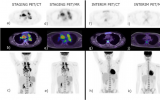

PET/MRI有望成為淋巴瘤診斷中PET/CT的有效替代方案

布里斯班亞歷山大公主醫院(Princess Alexandra Hospital)的Vijay Mistry博士領導的一個團隊對新診斷的霍奇金和非霍奇金淋巴瘤患者進行了同一天FDG-PET/MRI與FDG-PET/CT的診斷性能比較。這兩種方法幾乎完全匹配,但該小組認為PET/MRI更具優勢,因為它使患者受到的輻射更少。 2023-02-07